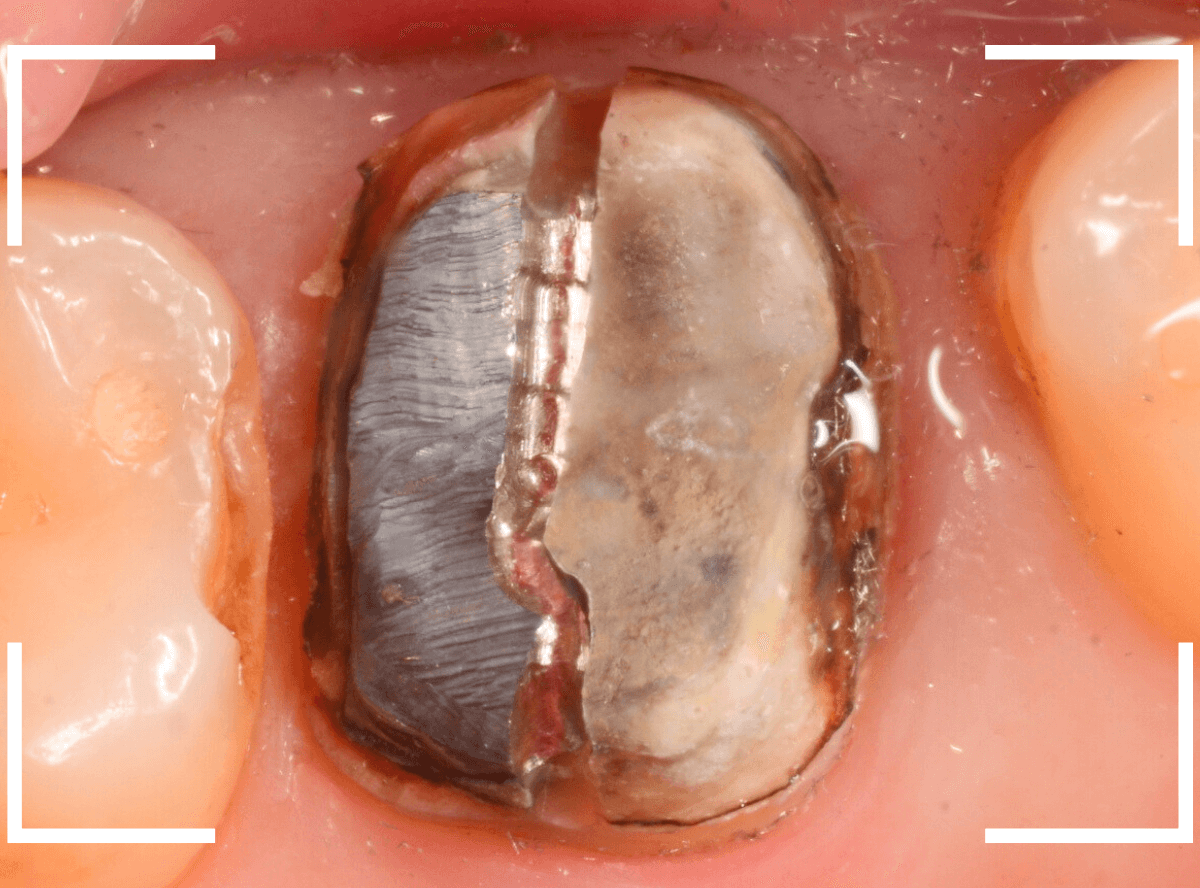

今回は、上の奥歯の銀歯(メタル・クラウン)の中で虫歯になってしまった方です。

通常は、さし歯の中が虫歯になってしまうと、レントゲンにも写らず見つけづらいのですが・・・。

歯を裏側から見たところです。

幸い、見える部分に虫歯が

さし歯と歯肉の間に虫歯ができているのがわかります。

歯の奥まで虫歯が進んでいるのか、浅い虫歯ですんでいるのかは治療をしながら調べていく必要があります。

さし歯を外すと、金属の土台(メタル・コア)が出てきました。

慎重に土台を外して、中を調べます。